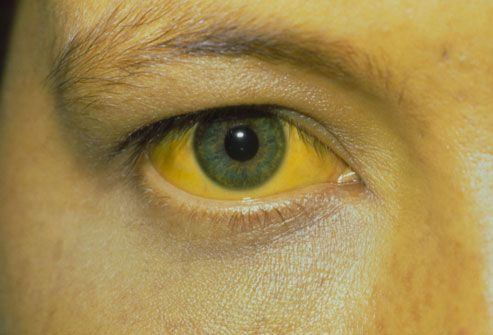

بیشتر بخوانید »خطرناکترین نوع هپاتیت کدام است؟

خطرناکترین نوع هپاتیت کدام است؟ معاون بهداشتی دانشگاه علوم پزشکی بیرجند گفت: هپاتیت به التهاب نسج کبد گفته میشود که در اثر عوامل متعددی مثل داروها، مواد توکسیک و ویروسها ایجاد میشود.دکتر کامبیز مهدیزاده، افزود: هپاتیت ویروسی توسط ویروسهای مختلفی ایجاد و به انواع A، B، C، D، E، G و F تقسیم میشود.معاون بهداشتی دانشگاه علوم پزشکی بیرجند ادامه …

بیشتر بخوانید »هپاتیت چگونه منتقل میشود؟

هپاتیت چگونه منتقل میشود؟ يك متخصص بیماریهای عفونی گفت:در حال حاضر با طرح واکسیناسیون کشوری که در نوزادان انجام میشود، هپاتیتB به مرحله کنترل رسیده است یعنی شیوع هپاتیت B در افراد کم خطر به 2/1 درصد از جمعیت مردم رسیده است.دکترمسعود مردانی، متخصص بیماریهای عفونی در گفتگو با برنامه «فراسو» شبكه راديويي سلامت با بيان اينكه وقتی التهاب در …